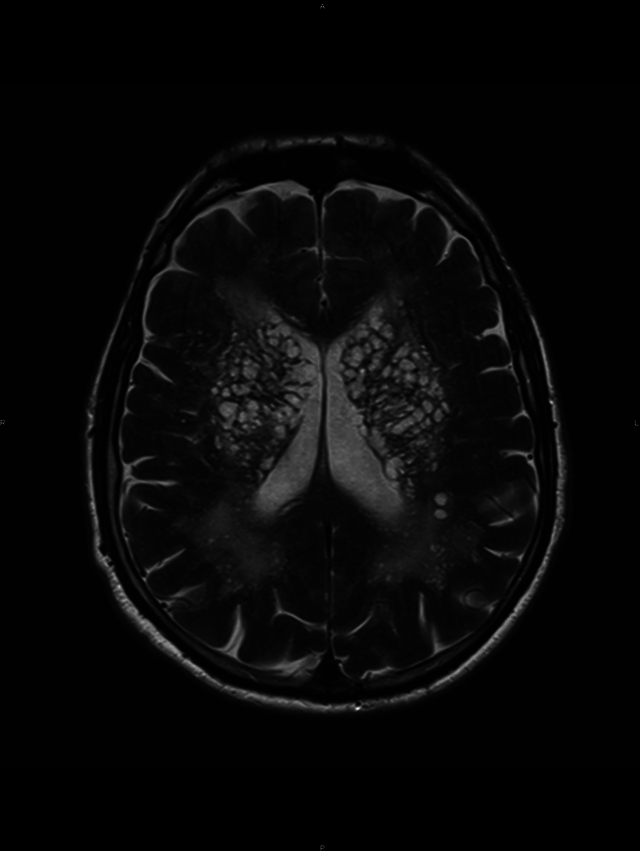

Teaching point: Perivascular spaces, also known as Virchow-Robin spaces, are fluid-filled spaces that surround the vessel walls from the subarachnoid space through the brain parenchyma.

Abstract Image